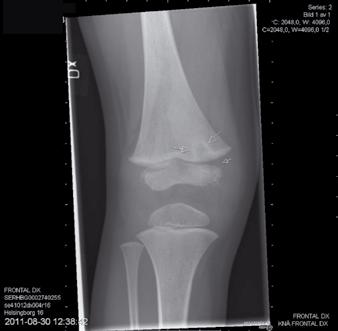

Figur 1a-d. Belastade fotbilder hos patient med bilateral spastisk cerebral pares med tydlig abduktion av framfoten på höger sida(fig 1a), där man på sidobilden (fig 1b) ser ett tydligt ”midfoot break” Patienten går med tåisättning på båda fötter och uppvisar tydlig hallux valgus bilateralt. Fig 1c visar peroperativa röntgenbilder, där laterala delen av foten förlängts genom insättning av strukturellt bengraft någon centimeter från leden mot cuboideum. Fig 1 d visar MTP I artrodes med stiftfixation på samma fot.

Figur 2a och b. Patient med valgusbelastad fot och hallux valgus interfalangeus Postoperativ bild där calcaneus förlängts så att framfotsabduktionen försvåras. Stortån har åtgärdats genom en kilosteotomi på grundfalangen.